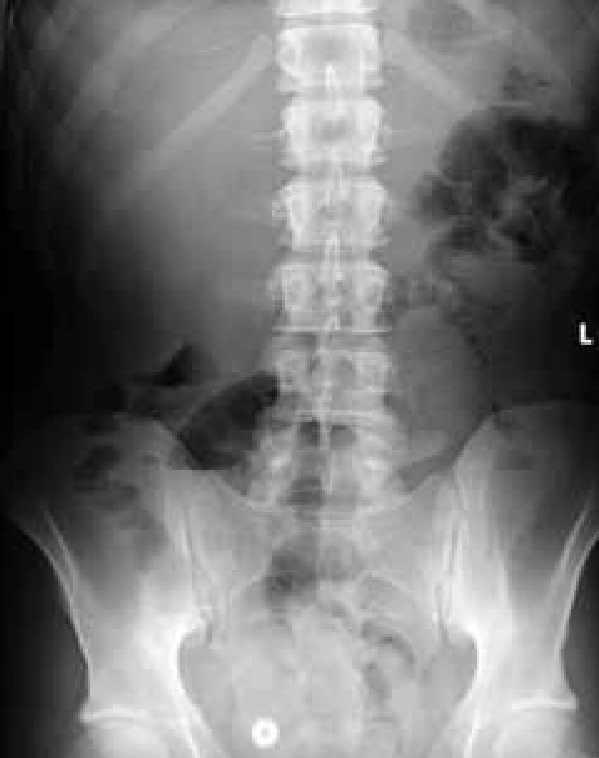

A 23-year-old man presented to the Surgery Department with acute right iliac fossa pain. Computed tomography revealed thickening of the terminal ileum. He was treated with ciprofloxacin and metronidazole with clinical improvement. One month later, he was referred to the Gastrointestinal Department for further evaluation. A slight elevation of CRP (10mg/L) and mild anemia (Hb:12mg/dL) were noted. Endoscopically, scarce aphthoid ulcers along the colon and an edematous ileocecal valve were detected. Intubation of the terminal ileum was impossible. Histology revealed infiltration of the epithelium by polymorphonuclear leukocytes and discontinuous inflammation with deep extension into submucosa; findings compatible with Crohn’s disease. Enteroclysis showed mild stenosis and filling defects of the terminal ileum wall suggestive of ulcerations [Fig. 1]. To determine the extent of the disease better, we decided to perform capsule endoscopy and an Agile® patency capsule was offered. Twenty hours later, the patient experienced severe right iliac fossa pain. X-ray imaging detected the capsule and air-liquid levels at the right iliac fossa [Fig. 2] and the patient was treated conservatively.

A few hours later the patient had fever (39.50 C) and diarrhea. CRP and ESR were 168mg/L and 85mm/h respectively. A new X-ray showed the capsule at the same point. The following day, X-ray failed to identify the most probably dissoluted capsule. However, due to the aggravating patient’s clinical status, i.v prednisolone was initiated. One day later, the patient had a remarkable clinical improvement, and the following days, CRP and ESR turned to normal.